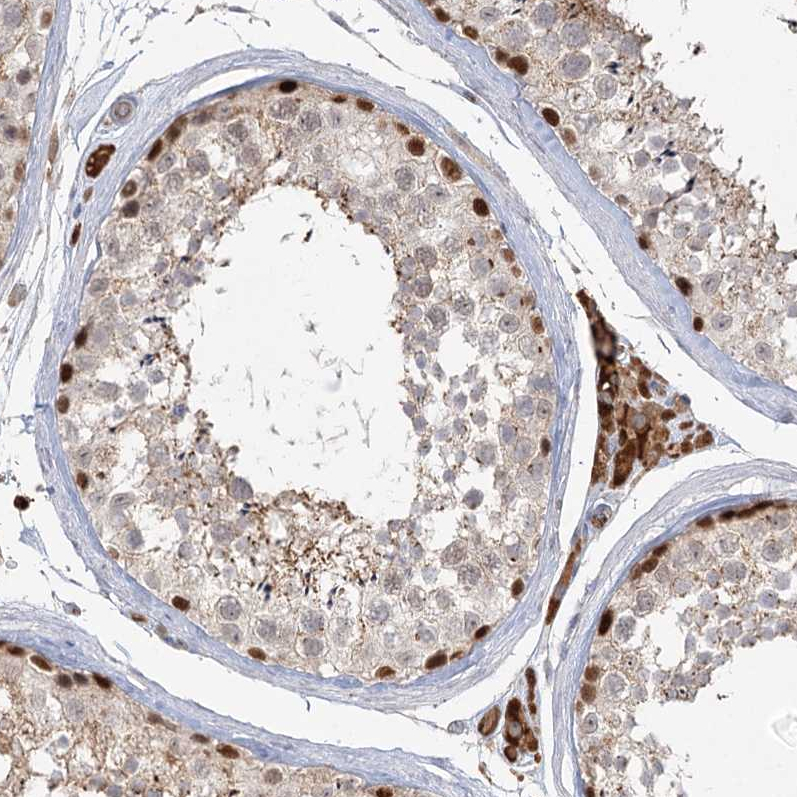

Immunohistochemical staining of human testis shows strong nuclear and additional weal cytoplasmic positivity in cells in seminiferous ducts and leydig cells.